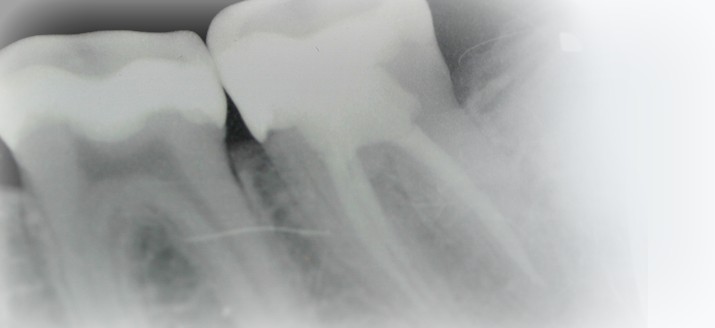

Dazu muss die Wurzellänge exakt bestimmt werden. Deshalb messen wir nicht nur röntgenologisch sondern zusätzlich auch elektrisch, um Messfehler zu vermeiden.